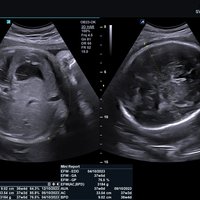

• SVC1-8H (1-8 MHz) für Ultraschalluntersuchungen in Bereichen Abdomen, Geburtshilfe, Gynäkologie, Urologie, Pädiatrie, EM